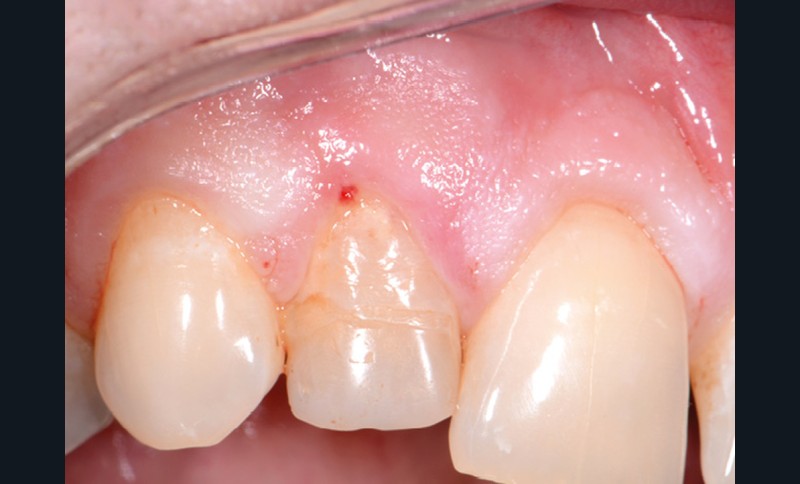

Perforation supra-osseuse (fig. 1)

Les perforations supra-crestales sont la plupart du temps iatrogéniques et surviennent lors de la réalisation de la cavité d’accès, ou de la recherche des entrées canalaires. Il s’agit généralement d’une communication avec un diamètre bien défini et aux contours nets. De ce fait, ce type de perforation est appelée « perforation à quatre parois ». Les perforations peuvent également être d’origine pathologique (résorption cervicale externe, carie active).

6. estimation du niveau de perforation : la situation décrite ici est celle d’une perforation supra-crestale, sous-gingivale, nécessitant la réalisation d’un accès chirurgical (lambeau d’accès) ;